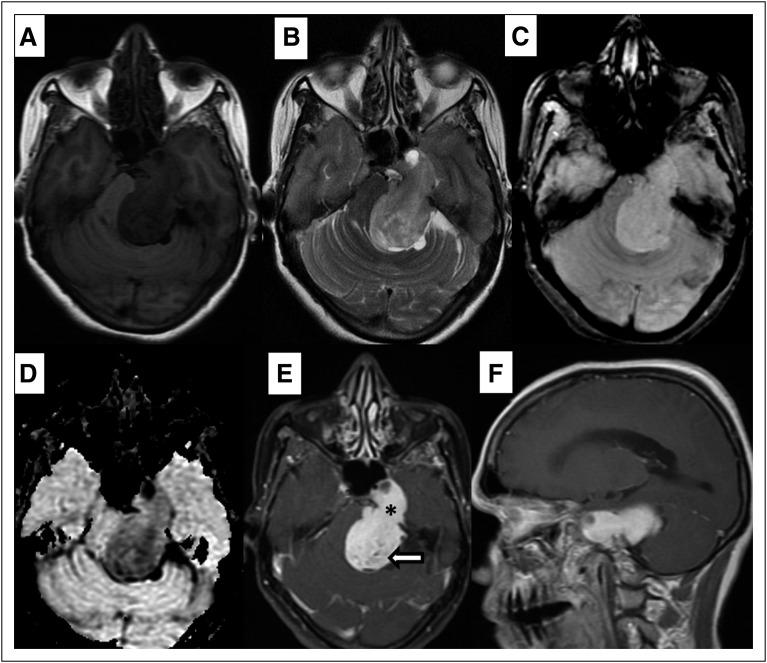

Multicompartmental trigeminal schwannomas (MTSs) are a rare and complex but treatable group of tumors. Herein, we describe the clinicoradiologic presentation of two patients with MTS. The two illustrated distinct case reports highlight the role of imaging and the outcome of two different types of MTS. The Discussion summarizes the literature to date, which will help the reader diagnose these tumors in a timely manner and manage them appropriately.